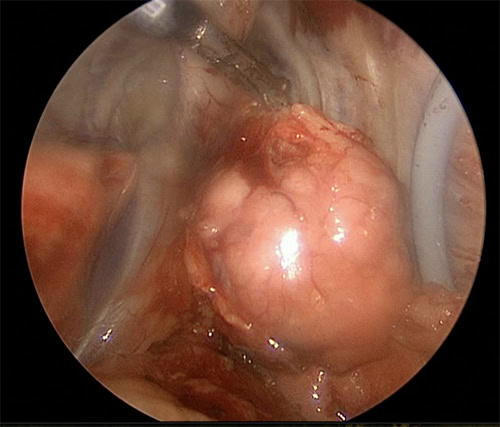

After discussion with our internal medicine team, surgical removal of the thymoma was recommended to the owners. The mass was small enough (3cm) to be removed by thoracoscopy (“key-hole” chest surgery) and so this was planned by our Soft Tissue team. Tommy was then anaesthetised and put onto single-lung ventilation by our anaesthesia team so that there was enough room within the chest for the surgeons to safely remove the mass. The tumour was completely removed and Tommy recovered very smoothly in our ICU department staffed by our ECC (emergency and critical care) team. Tommy was very bright and comfortable the day after surgery and was discharged that afternoon. Tommy went on to recover uneventfully from his surgery and is currently doing very well. Not only does he no longer have a tumour growing in his chest but his original lameness has resolved and he is out enjoying his walks again!